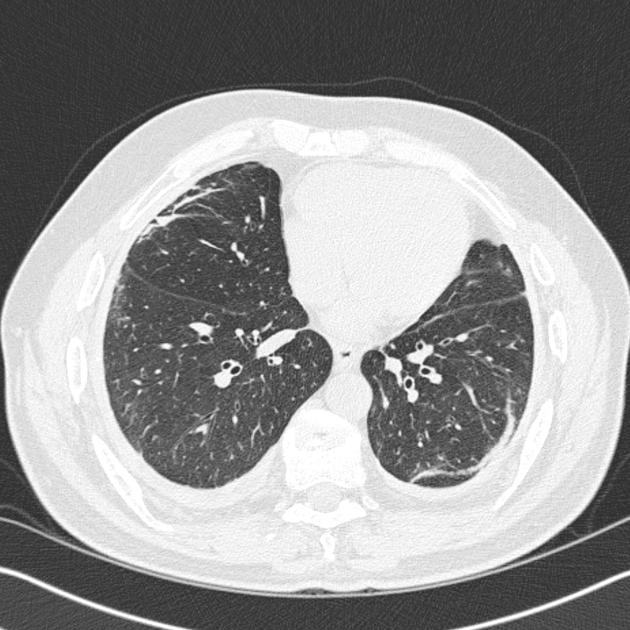

- Рентгенография органов грудной клетки (РОГК): Рентген легких не является стандартным методом диагностики бронхиолита. В большинстве случаев типичная клиническая картина позволяет поставить диагноз без рентгенологического исследования. РОГК показана в следующих ситуациях:

- Атипичное течение заболевания.

- Подозрение на осложнения, такие как бактериальная пневмония, ателектаз (спадение части легкого) или плевральный выпот.

- Выраженная дыхательная недостаточность, не соответствующая легкой или средней тяжести бронхиолита.

- При наличии сопутствующих заболеваний легких или сердца.

- У младенцев с длительной лихорадкой или ухудшением состояния после начального улучшения.

На рентгенограмме при бронхиолите могут наблюдаться признаки гипервоздушности легких (увеличение прозрачности легочных полей), утолщение стенок бронхов (перибронхиальные утолщения) и ателектазы небольших участков легкого. Эти изменения подтверждают поражение мелких бронхиол, но не всегда специфичны.

Другие методы, такие как компьютерная томография (КТ) легких, ультразвуковое исследование легких или бронхоскопия, при бронхиолите обычно не применяются и используются только в крайне редких, диагностически сложных случаях или при подозрении на специфические осложнения.